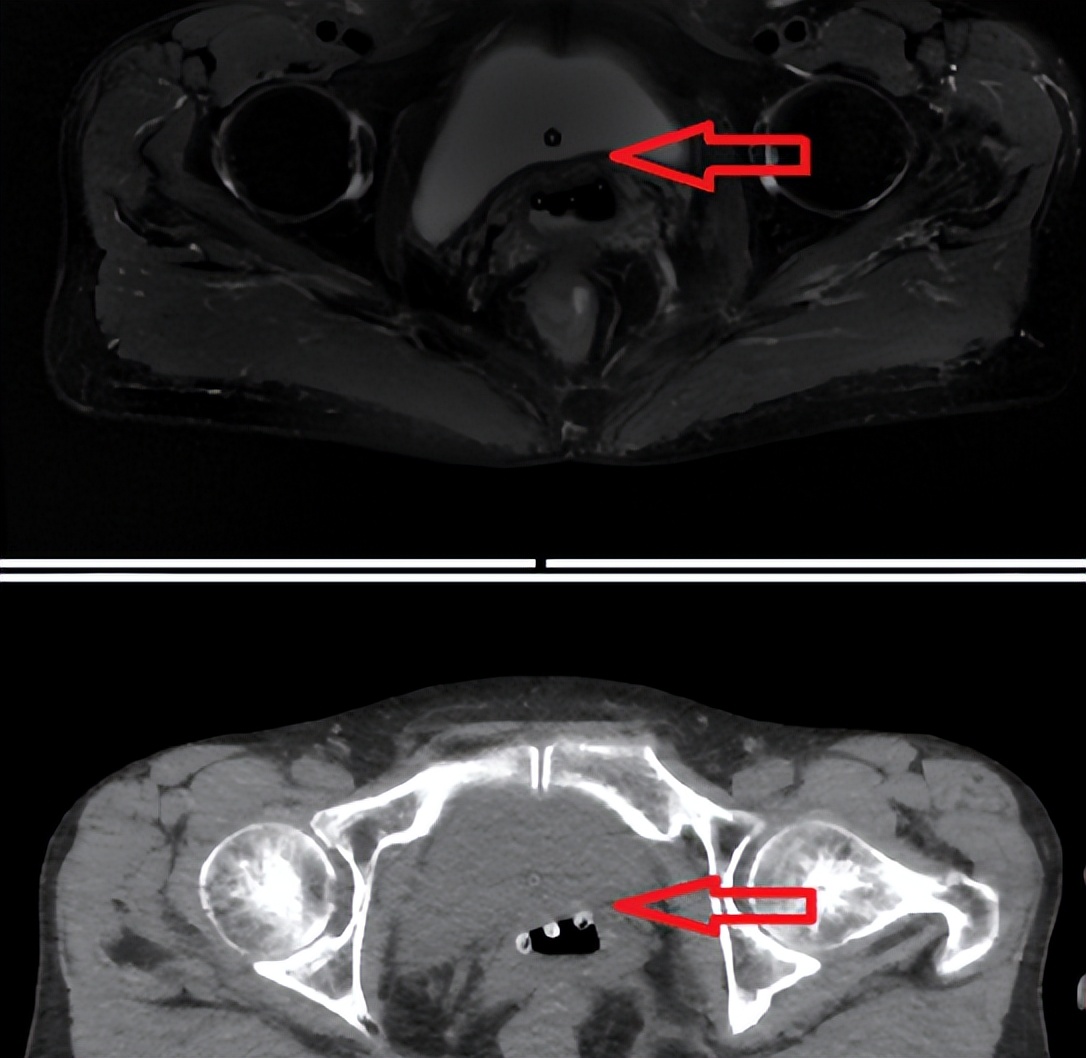

可在术前对病灶进行准确定位、定性、临床分期及确定是否有淋巴结转移及远处转移。为了使临床分期更加准确,对患者进行个体化治疗,2018 年 FIGO 分期规定将影像学检查结果应用于临床分期,更加肯定了影像学在患者临床分期中的地位。

一系列综述指出PET/CT 相对于 CT 和 MRI 来说在淋巴结转移方面有较高的诊断价值,MRI 诊断淋巴结转移,单纯依靠形态学表现,而 PET/CT可在从生理代谢层面预测淋巴结的良恶性。

18F-FDGPET/CT在远处转移灶的检出方面同时具有较明显的优势,能够对主动脉旁、锁骨上窝处出现的转移淋巴结及腹膜、大网膜和其他组织器官的转移灶进行准确的判断。

六、PET/CT在淋巴结良恶性中的应用

18F-FDG PET/CT 在宫颈癌临床分期应用广泛,且在淋巴结转移方面有独特的诊断价值。大量研究证明传统的淋巴结清扫术取得的淋巴结标本 90%以上为良性淋巴结,预防性质的较大范围的淋巴结清除常常会引起淋巴囊肿、神经血管损伤及术后粘连等并发症。

因此术前对于淋巴结转移的正确识别具有重要意义。MTV、TLG 常用来反应病灶肿瘤负荷情况,MTV 代表勾画的病灶体积,而 TLG 则为SUV 和 MTV 的乘积,包含病灶的生物代谢信息和体积的双重因素。

但通过阅读近年来文献发现,关于 MTV 应用于盆腔淋巴结的研究较少。Yang等研究结果表明,MTV 预测淋巴结转移的最佳界值为 0.5cm3,其相应敏感度为 46.2%,特异度为94.0%。

判断淋巴结转移的传统诊断标准之一是淋巴结的短径﹥1cm,尽管诊断效能不如 SUVmax,但仍具有较高的特异性。KANG等研究发现 SUVmean 相对于其他 PET/CT 代谢参数在预测淋巴结方面具有更高的准确度。